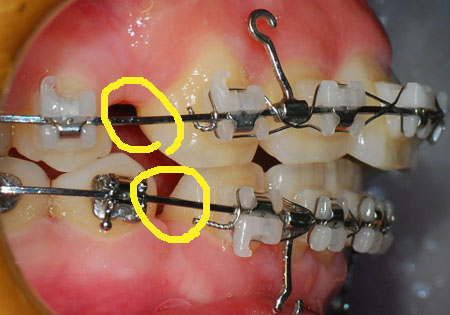

측면 사진

저기 동그라미 친 부분이 남은 발치 공간 입니다. 많이 줄어들엇죠?

친구가 저 틈을 보고 치아 뽑은지도 몰르더라구요ㅋㅋㅋ

노란 동그라미는 남은 발치 공간 입니다.

예전에 처음 교정 할 때 이가 전체적으로 앞으로 나와서

뒤에 이들이 앞으로 쏠려 있어서 공간이 있다고 했었는데요.

지금 파란 동그라미 보시면 그 공간이 거의 없습니다. 음하하하하하하핳

신기하게 많이 변하네요